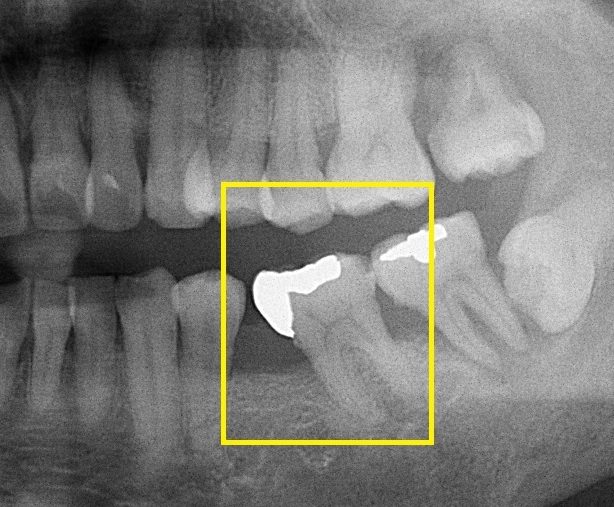

이어 백 교수는 "치료의 적기를 놓치면 멀쩡한 치아에 하지 않아도 됐을 치료를 하게 돼, 훨씬 더 큰 비용과 시간이 소요될 수 있고, 치료 결과도 좋지 않을 가능성이 높다"라며, "치아가 망가졌다면 가능한 한 빨리 치과 방문 후 적절한 치료를 받는 것이 필요하다"라고 조언했다고 합니다. 치아가 빠진 자리를 수복하는 방법에는 브릿지, 틀니 그리고 임플란트 등이 있습니다. 치아가 빠진 위치나 골상태, 주변 치아 상태 등에 따라 선택하게 되는 치료 방법은 달라집니다.

대표적인 치료 방법인 임플란트는 인공 뿌리를 심고 그 위에 치아 머리를 수복하는 것으로, 주변 치아의 손상 없이 구조를 복원할 수 있습니다. 임플란트 치료 기간은 발치 후 임플란트 심기 전까지의 대기시간과 임플란트를 심은 후 상부 보철물을 씌우기까지 대기시간에 따라 결정된다고 합니다. 전통적인 과정은 발치 후 3~4개월 정도를 기다려 치아의 뿌리가 있던 공간에 뼈가 어느 정도 차면, 임플란트를 심습니다. 이후 3개월 이상 기다려 뼈와 임플란트가 완전히 붙으면 보출물을 씌웁니다.

백연화 교수는 "최근에는 임플란트 디자인 및 표면 처리 방법 외에도 수술 기법 등이 발달해 6~8주 정도로 치료 기간이 짧아지고 있는 추세"라며, "제한적인 경우에 한해 발치 당일 임플란트 수술 및 임시 보철물까지 즉시 연결하기도 한다"라고 말했습니다.